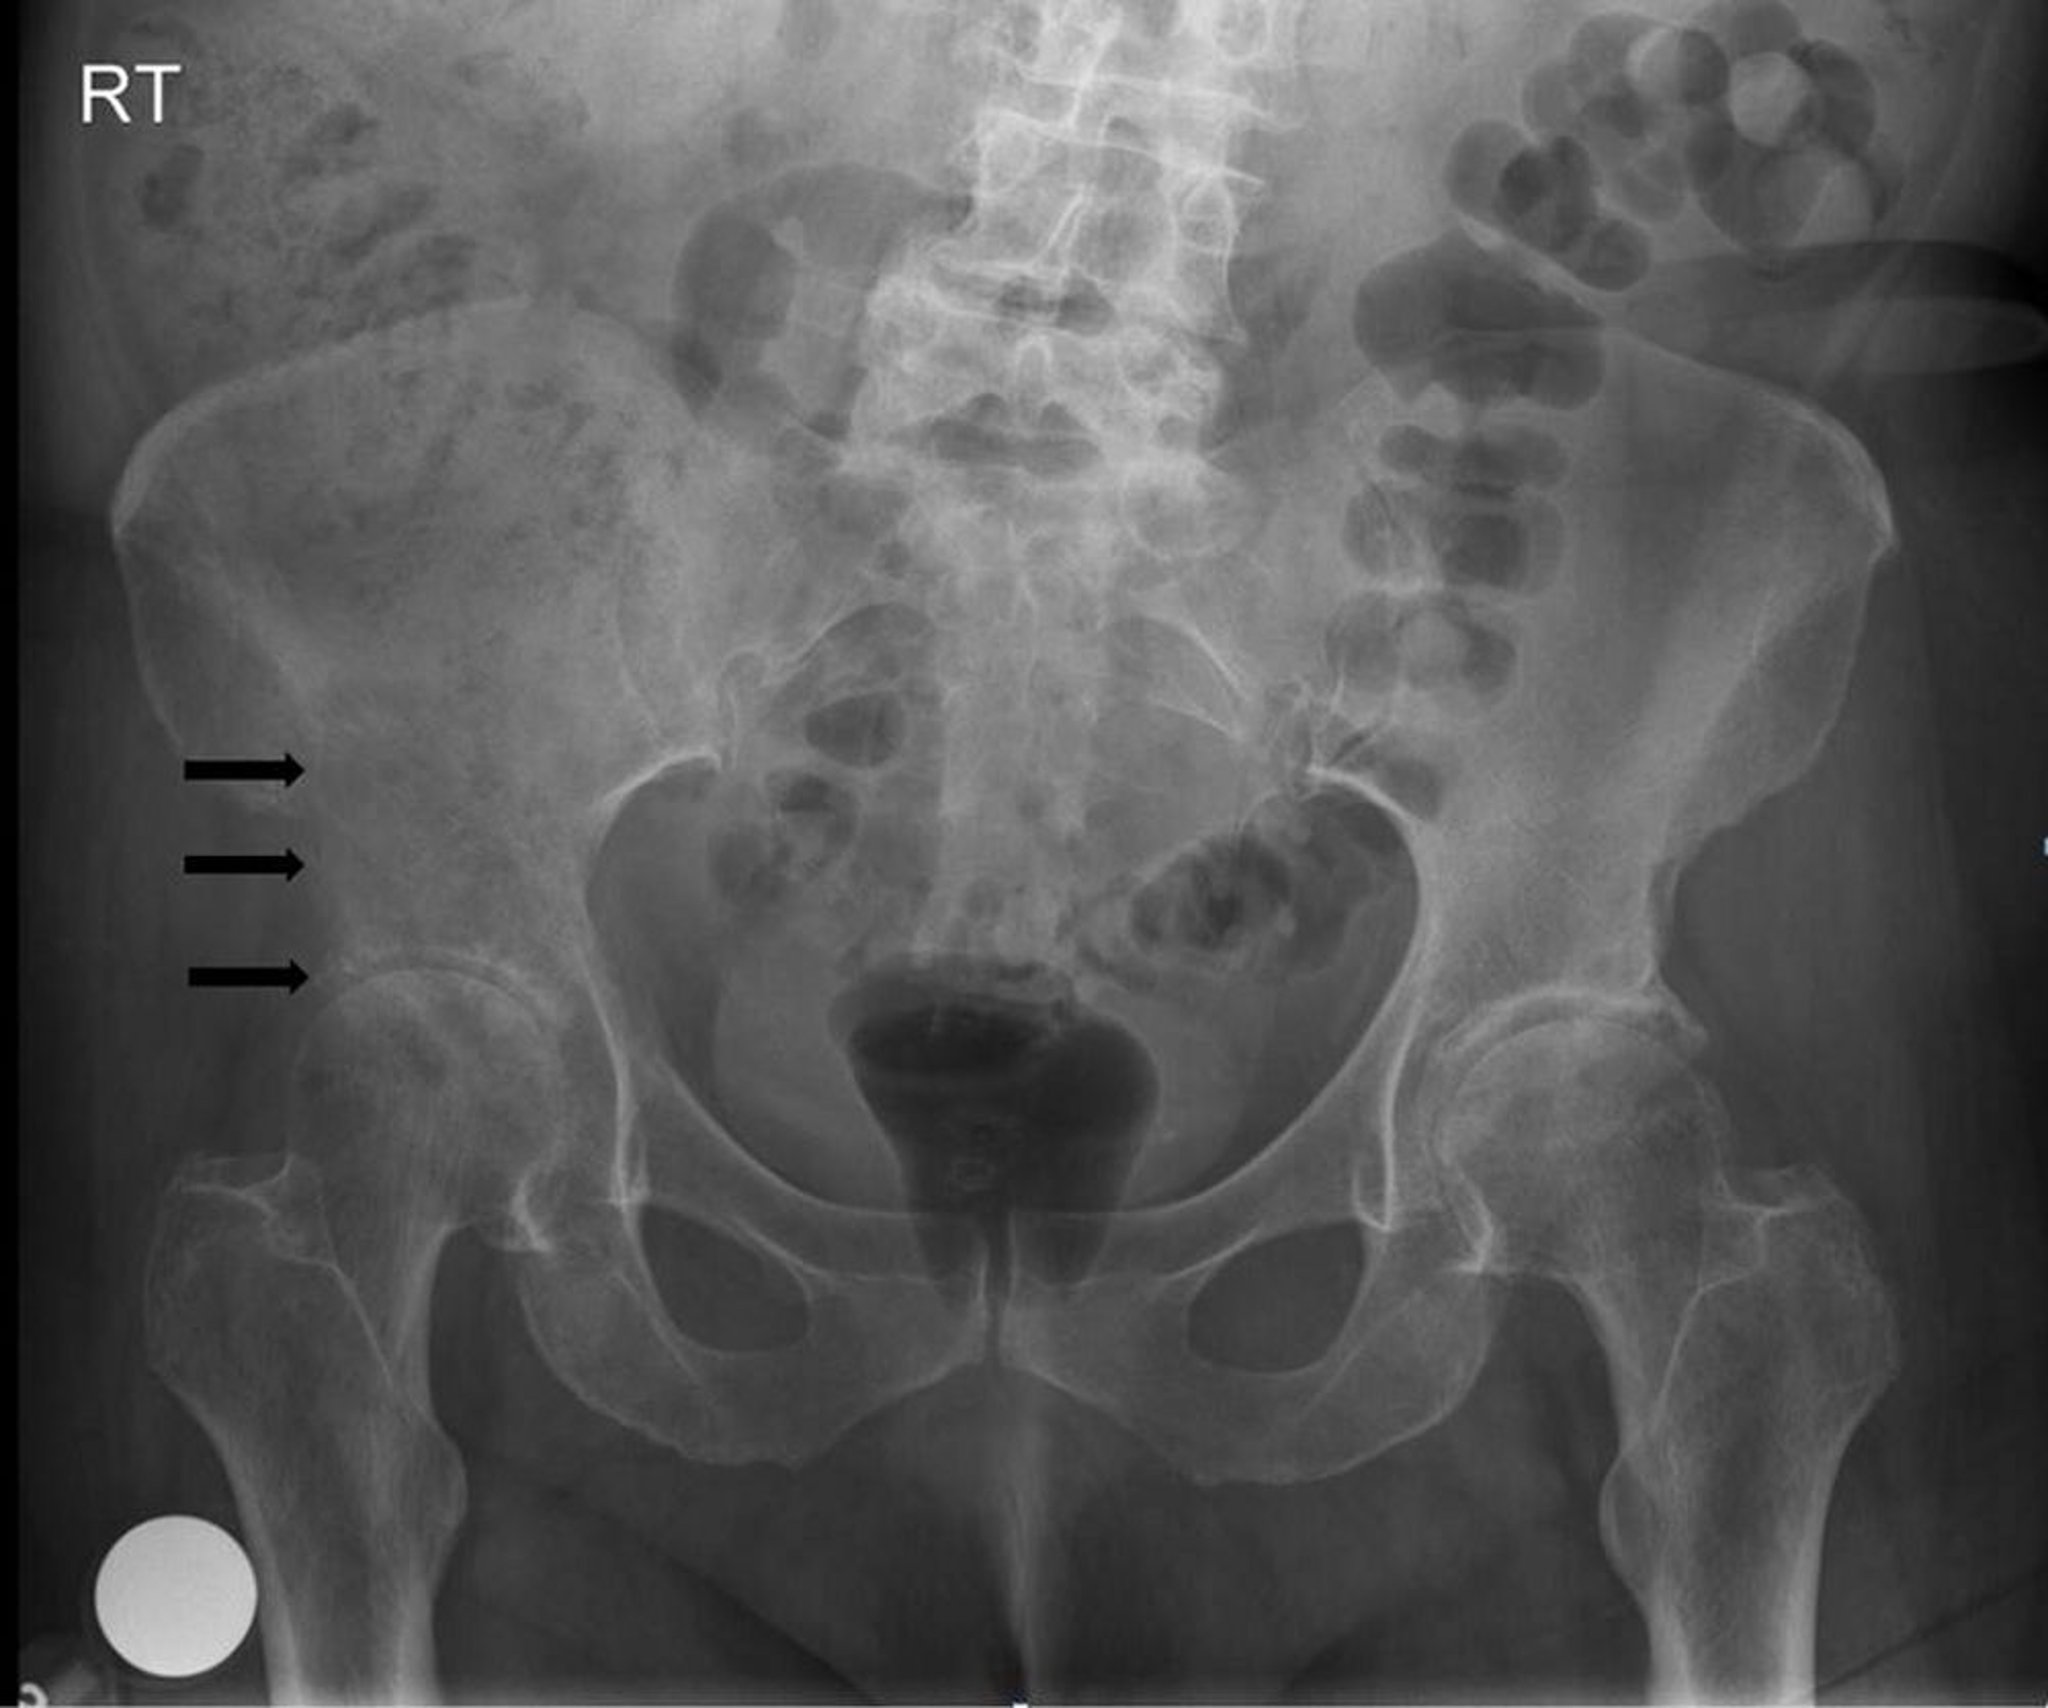

Tumor óseo metastásico

Esta radiografía de la pelvis muestra una lesión lítica y destructiva en y por encima del acetábulo derecho (flechas), compatible con una metástasis.

Image courtesy of Michael J. Joyce, MD, and Hakan Ilaslan, MD.